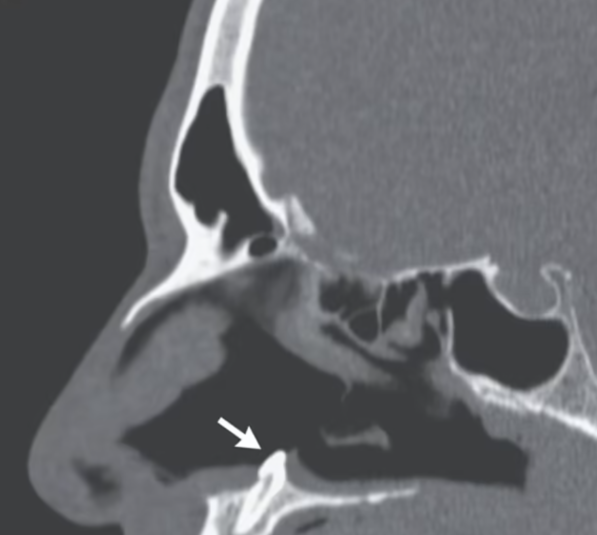

У Нью-Йорку в 38-річного чоловіка медики виявили справжній зуб у носі. Стаття про це з'явилася в науковому журналі The New England Journal of Medicine, пише Mail Online.

Чоловік скаржився, що кілька років має проблеми з диханням через праву ніздрю. Провівши риноскопію за допомогою камери та ліхтарика, лікарі виявили в носі «тверду безболісну білу масу». З'ясувалося, що це 14-міліметровий ектопічний зуб.

Чоловікові зробили успішну операцію і видалили зуб. Через три місяці проблеми з диханням припинилися.

Хоча ектопічні зуби зустрічаються частіше, ніж інші ектопічні частини тіла, у носі вони з'являються вкрай рідко.